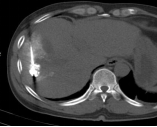

社会快速发展所带来的环境影响,让肿瘤离我们越来越近,当身边的人患有这种疾病时,给患者和亲人带来沉重的思想包袱,而开刀、化疗、放疗等传统治疗方式又给肉体带来更加痛苦的深层次打击。 患者往往对传统治疗望而却步,在绝望中等待生命的终结…… 问 还有希望吗!还有别的治疗方法吗? 答 有!而且还很易于接受。 一根细针,一根细细的PVC导管,或许就能给你带来希望。 通过细针,经皮穿刺病灶,取得细胞学、组织学等资料,可以让我们了解到底是恶性肿瘤还是良性疾病,并知道是什么类型的肿瘤;通过细针,可以让针尖加热,把肿瘤加热失去活性,就像把鸡蛋煮熟了再也孵不出小鸡那样,肿瘤就不再生长,而逐渐吸收变小;通过细针,可以把小小的粒子植入肿瘤,通过粒子缓慢释放能量,把肿瘤灭活,达到治愈肿瘤病灶的目的。 通过导管,进行血管造影进一步确认到底是不是恶性肿瘤;通过导管,并可把载有抗肿瘤药物微球直接注射进入肿瘤血管,缓慢持续长时间杀灭肿瘤细胞;通过导管,可以把给肿瘤供血的血管堵起来,让肿瘤失去血流,失去养料供给,饿死它。 上帝为你关上一扇门的同时,必定会为你打开了另一扇窗,快速发展的社会,科技日新月异,新技术新方法也给肿瘤治疗带来了新的希望。 近年来,淄博市中医医院介入科引入诸多新时代发展带来的前沿新技术,结合数千年古老神秘的中医调理,给诸多患者带来了新的希望和愉快的新生活。 病例一 2015.9 2015.9.11微波消融后 2017.4 肝动脉栓塞并粒子植入,病变直径75mm 2021.4.复查,病变直径35x23mm 病例二 2015.7 肝动脉栓塞并肝癌微波消融 2017.8 MRI复查,病变未见进展 2021.7 CT复查病灶显著缩小 患者后期按时复查,其他处有新增病灶,通过多次介入治疗,至今健在。 介入放射学 是在现代影像学(DSA、CT、超声、磁共振等)方法的引导下,采取经皮穿刺、插管,对患者进行血管造影、采集病理学、生理学、细胞学、生化学检查资料,进行药物灌注、血管栓塞或消融等"非外科手术"方法诊断和治疗多种疾病。 其特点简便、安全、有效、微创、可重复治疗和并发症少,该技术也适合肺癌、肾癌、胰腺癌、甲状腺结节、肺结节等疾病的治疗。 它将不能治疗的疾病变为可治疗、难治性疾病变为容易治疗、复杂治疗疾病变为简单治疗、大创伤治疗变为微创治疗、危险治疗疾病变为安全治疗。目前许多介入方法成为了主要的治疗方法,甚至取代或淘汰了原来的外科手术。 淄博市中医医院介入科 0533-6699127、6699128 官方微信公众号 长按关注 获取更多健康咨询 淄博市中医医院 淄博市中医医院始建于1952年,是鲁中地区最大的一所集医疗、科研、教学、养生保健四位一体的综合性三级甲等中医医院。是山东中医药大学的附属医院、国家住院医师规范化培训基地、山东省中医药预防保健服务中心。设有21个临床科室,9个医技辅助科室,开放床位700张。医院拥有核磁共振、CT等大型诊疗设备300多台件。 预约电话:0533-6699333、6433111 新院区地址:周村区新建东路1166号(碧桂园对面) 。 电话:0533-6699333、6433111 1.乘坐96路公交车到碧桂园站下车 2.乘坐291路公交车到碧桂园站下车 3.乘坐258路公交车到碧桂园站下车 老院区地址:山东省淄博市周村区新建中路75号(乘坐238路、239路、34路、96路公交车均可到达) 和平路院区地址:张店区和平路18号(南西五路与和平路转盘东北角) 电话:0533-2210092 1.乘坐35路、121路、132路、95路公交车和平小区站下车北行100米即到。 2.乘坐138路、223路公交车天星小区站下车东行200米即到。 3.乘坐96路、126路、12路公交车中国陶瓷馆站下车南行600米即到。官方抖音